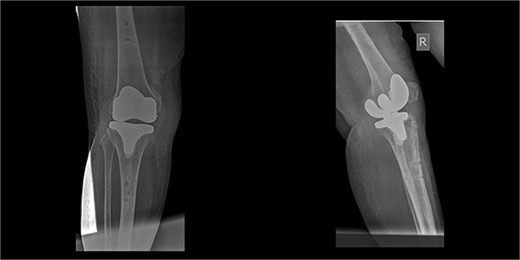

The external fixator was removed after 6 weeks (Fig. 6), and physical therapy was initiated. The patient’s postoperative course was uncomplicated. One week upon removal, 0°–80° of flexion was achieved through everyday kinesiotherapy. On her last visit, 1 year postoperatively, the patient was ambulatory, with knee ROM of 0°–100° (Fig. 7). No further abnormal neuromuscular signs were observed.